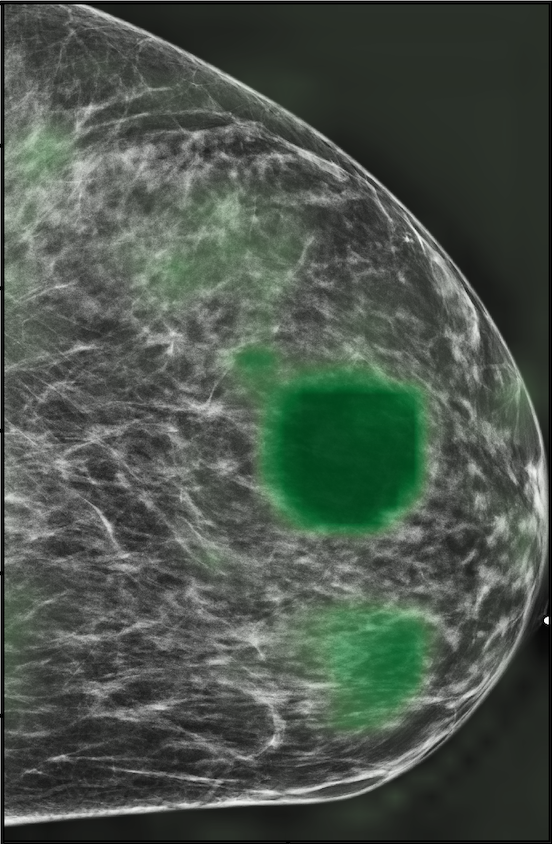

The NYU Breast Cancer Screening Dataset [78] includes 229,426 exams (1,001,093 images) from 141,472 patients.222Our retrospective study was approved by our institutional review board and was compliant with the Health Insurance Portability and Accountability Act. Informed consent was waived. Each exam contains at least four images which correspond to the four standard views used in screening mammography: R-CC (right craniocaudal), L-CC (left craniocaudal), R-MLO (right mediolateral oblique) and L-MLO (left mediolateral oblique). An example is shown in Figure 3.

Across the entire dataset (458,852 breasts), malignant findings were present in 985 breasts () and benign findings in 5,556 breasts (). All findings are confirmed by at least one biopsy performed within 120 days of the screening mammogram. For the remaining screening exams that were not matched with a biopsy, we assigned labels corresponding to the absence of malignant and benign findings in both breasts. In each exam, the two views of the same breast share the same label.

For all exams matched with biopsies, we asked a group of radiologists (provided with the corresponding pathology reports) to retrospectively indicate the location of the biopsied lesions. This way we obtained the segmentation labels: where if pixel belongs to the benign/malignant findings. An example of such a segmentation is shown in Figure 3. In all experiments (except for experiments in Section 3.6 that assess the benefits of utilizing segmentation labels), segmentation labels are only used for evaluation. We found that, according to the radiologists, approximately of exams were mammographically occult, i.e., the lesions that were biopsied were not visible on mammography, even retrospectively, and were identified using other imaging modalities: ultrasound or MRI.